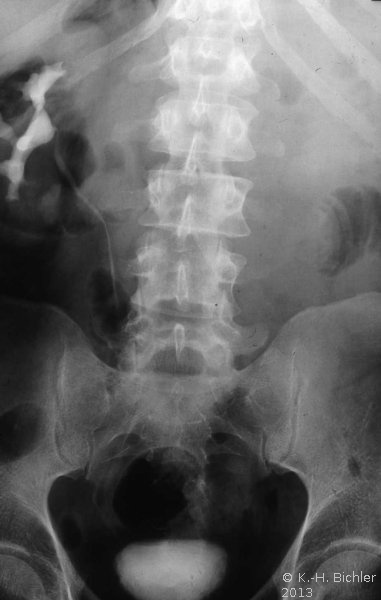

Die Röntgenübersicht der Niere und ableitenden Harnwege zeigten keinen Anhalt für Konkrement. Im Ausscheidungsurogramm eine "stumme Niere" links (Abbildung 19a). Bei der retrograden Sondierung links fand sich keine Abflussbehinderung (Stein oder Stenose) (Abbildung 19c). Im MCU kein Anhalt für Reflux (Abbildung 19b). Im Nierenfunktionsszintigramm MAG3 wurde eine seitengetrennte Funktionsverteilung von rechts zu links wie 93% zu 7% festgestellt. Zur Abklärung eventueller Gefäßalterationen erfolgte eine Renovasographie mit dem Nachweis einer langstreckigen Stenose der linken Arteria renalis (Abbildung 19d). Wegen des Verdachtes auf eine generalisierte Arteriitis wurden Angiographien weiterer Gefäßgebiete durchgeführt: Dabei fanden sich eine geringgradige Einengung der infrarenalen Aorta und der linken Arteria subclavia.